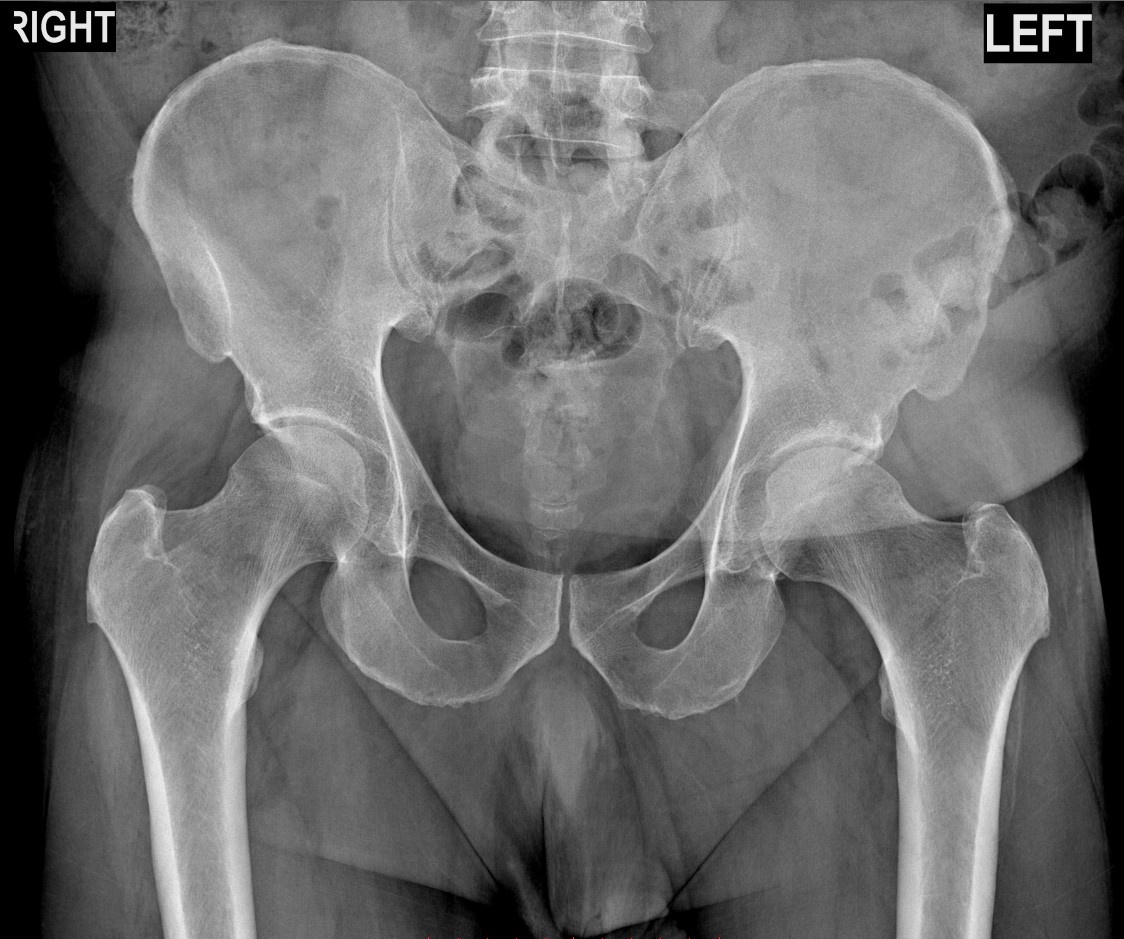

Случай 1: Дисфункция крестцово-подвздошного сочленения (КПС)

У пациента в анамнезе — эндопротезирование тазобедренного сустава и разная длина ног. Это привело к нарушению биомеханики и перегрузке КПС — того самого сустава, который соединяет таз с крестцом. Именно его дисфункция давала знакомую боль.